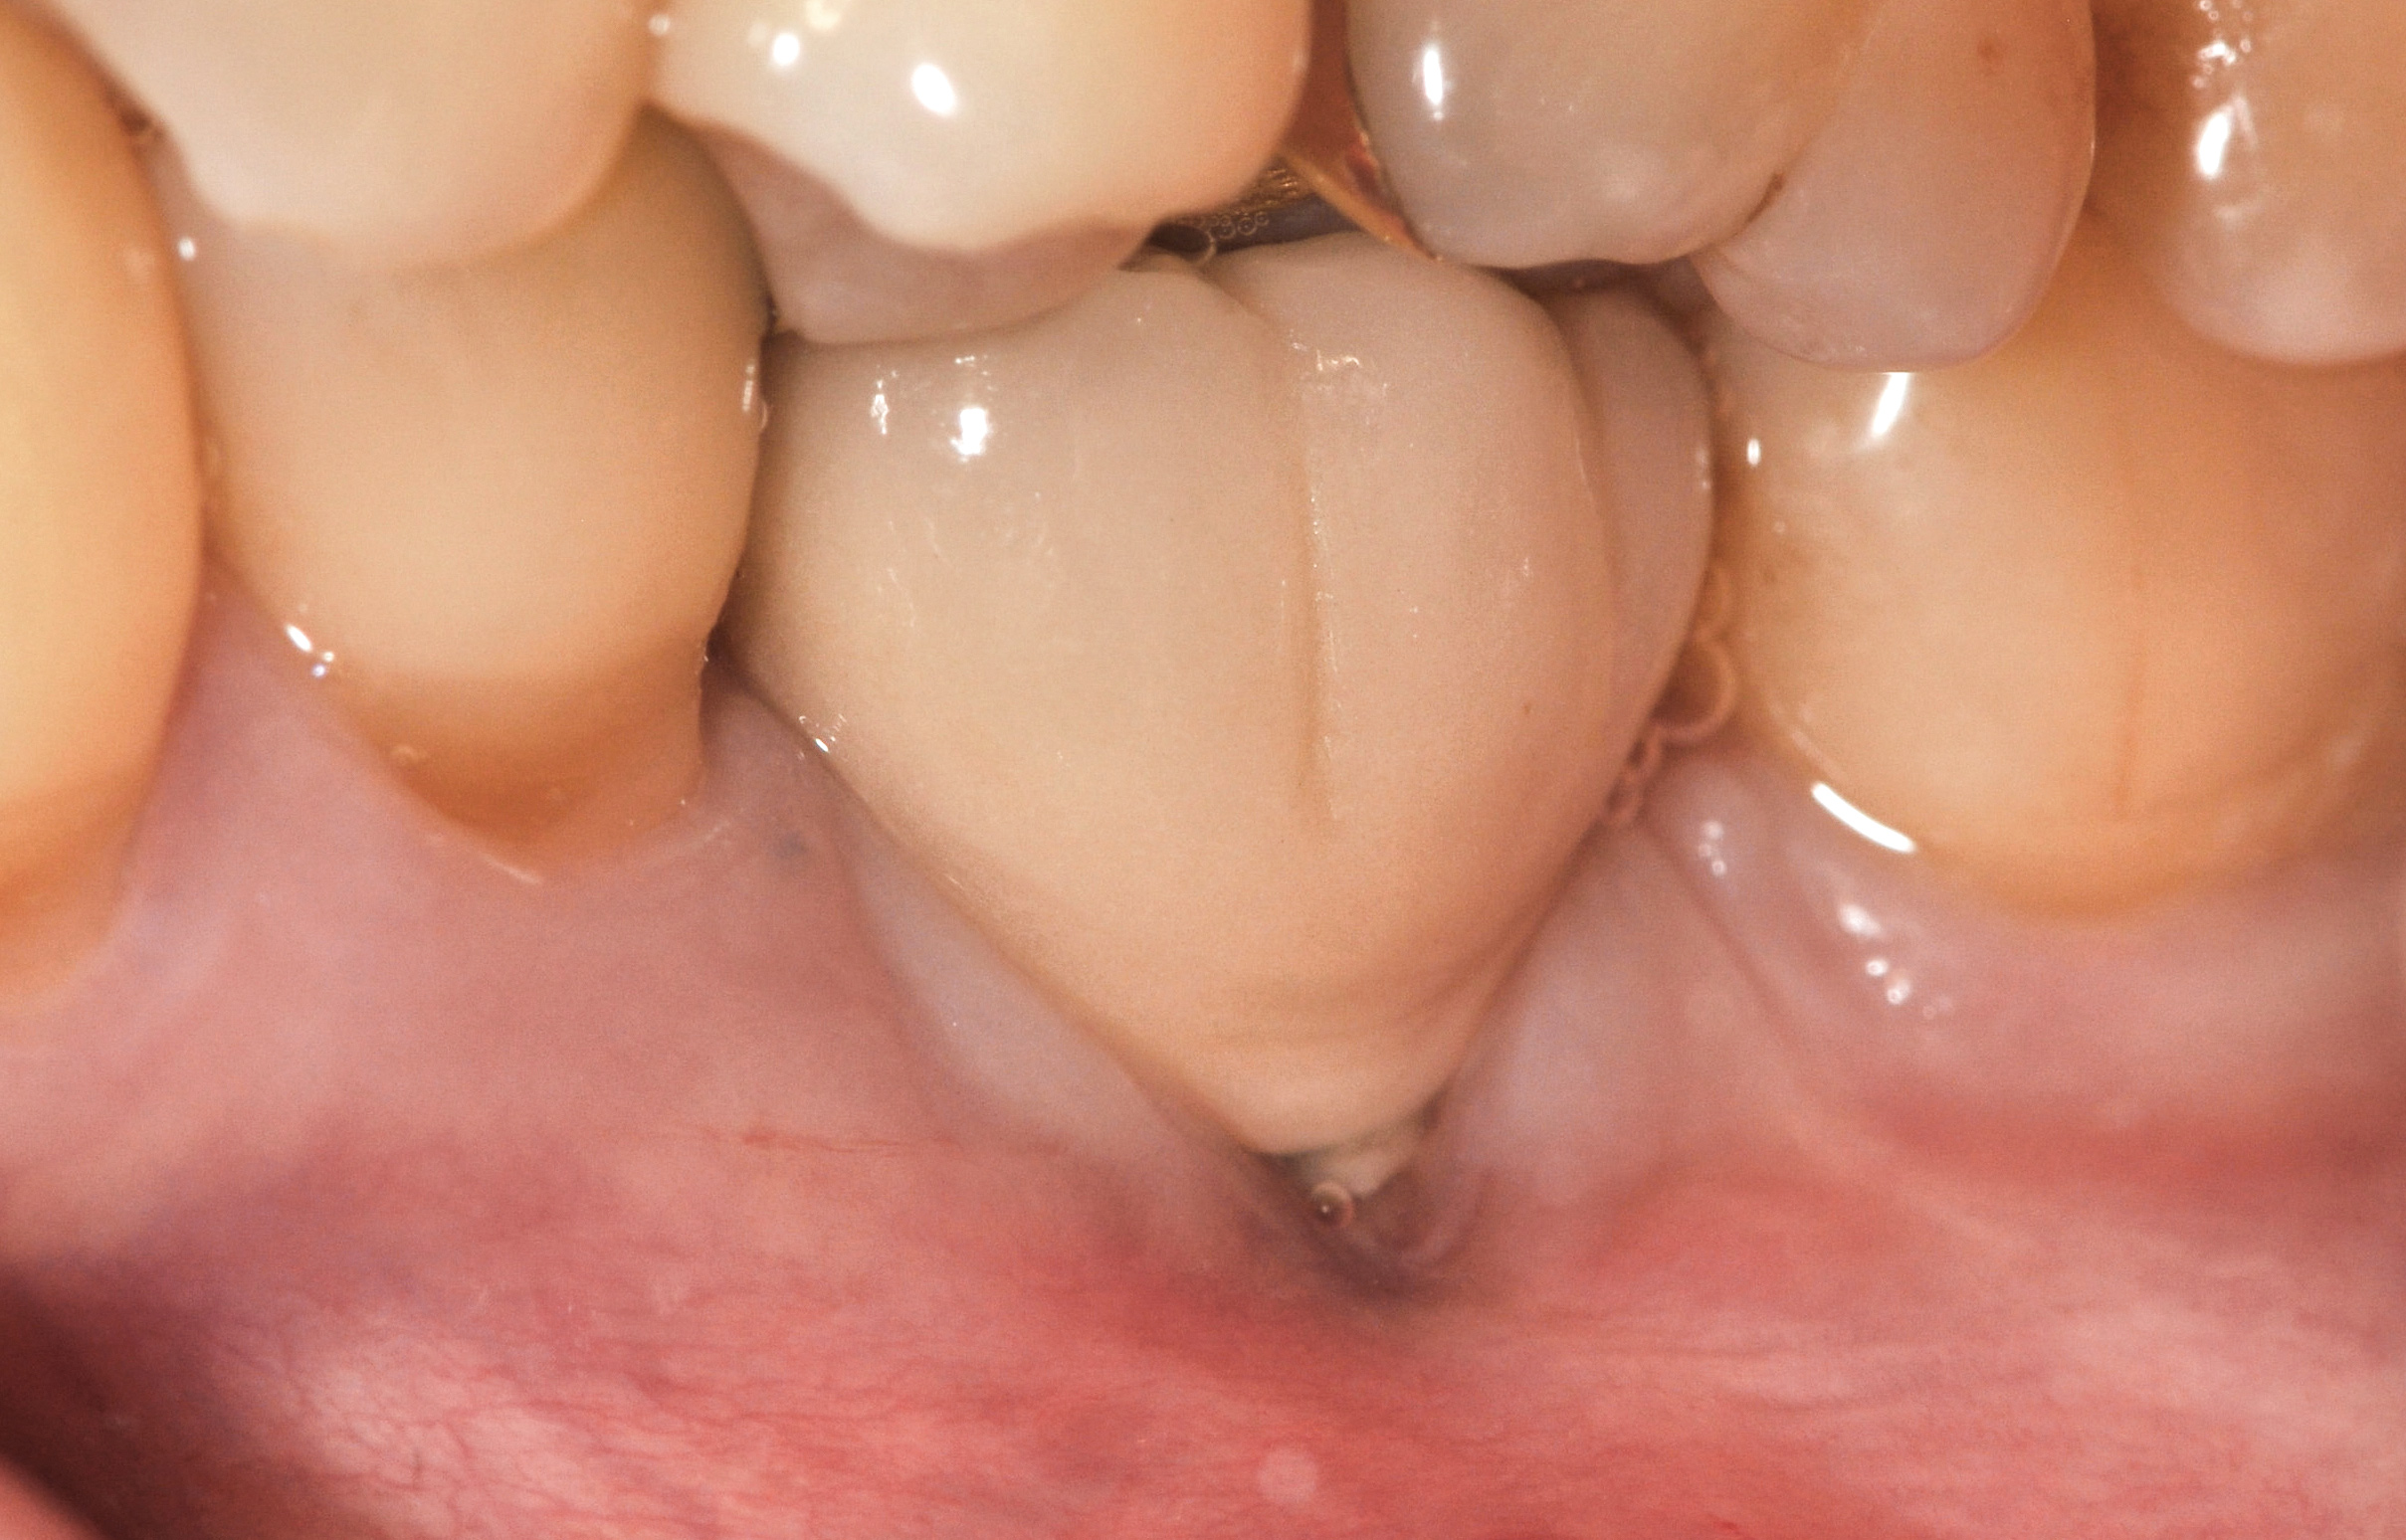

Fig 4. Intraoral view of tooth No. 7 with the gingival zenith more apical than the adjacent central incisor and canine tooth.

Figure 4

The following case report provides an example of this case scenario: A 28-year-old white female patient presented with her maxillary right lateral incisor significantly longer than the contralateral tooth following restoration of an existing crown that was 10 years old (Figure 3). The patient was dissatisfied with the esthetic appearance of the restoration due to the increased length, recession of the gingival tissues, and discoloration of the surrounding mucosa (Figure 4). Similar to case scenario No. 1, the first step in treatment was to decoronate the healthy implant by placing a flat surgical cover screw and employing a provisional resin-bonded-retained (RBR) prosthesis as a transitional fixed restoration (Figure 5 and Figure 6). The gingival augmentation in situ was allowed to take place for 2 to 3 weeks and was evaluated after that time (Figure 7).